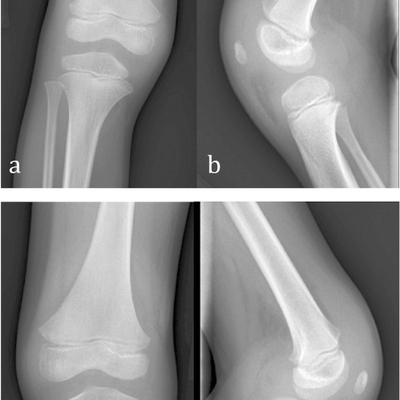

Click on an image below to view more info.